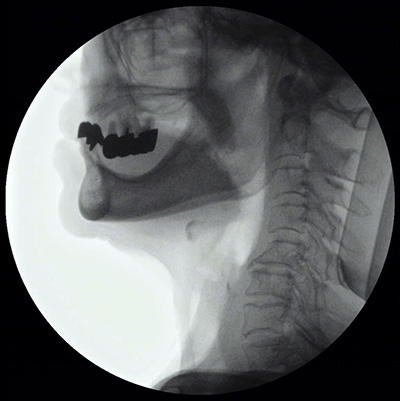

嚥下造影検査(VF)

「食べる・飲み込む」といった摂食嚥下機能に障害がある患者さまに対し、エックス線検査室でエックス線を照射しながら行う飲み込みに関する検査です。バリウムを混ぜた飲み物や食べ物を実際に口にし、どのように口から胃へ運ばれていくか、一連の流れを録画しながら確認します。専門医と言語聴覚士にて評価を実施し、嚥下機能の問題点を明らかにし、経口摂取が安全にできる姿勢や食事形態の工夫などを治療の方針に役立てています。